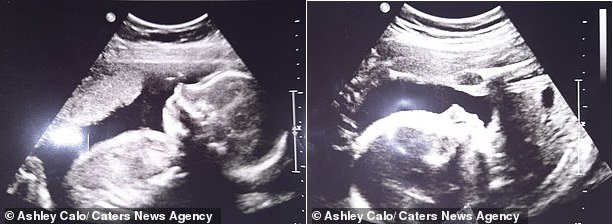

Hình ảnh siêu âm của Zoey và Parker. Hai bé ở trong hai tử cung khác nhau.